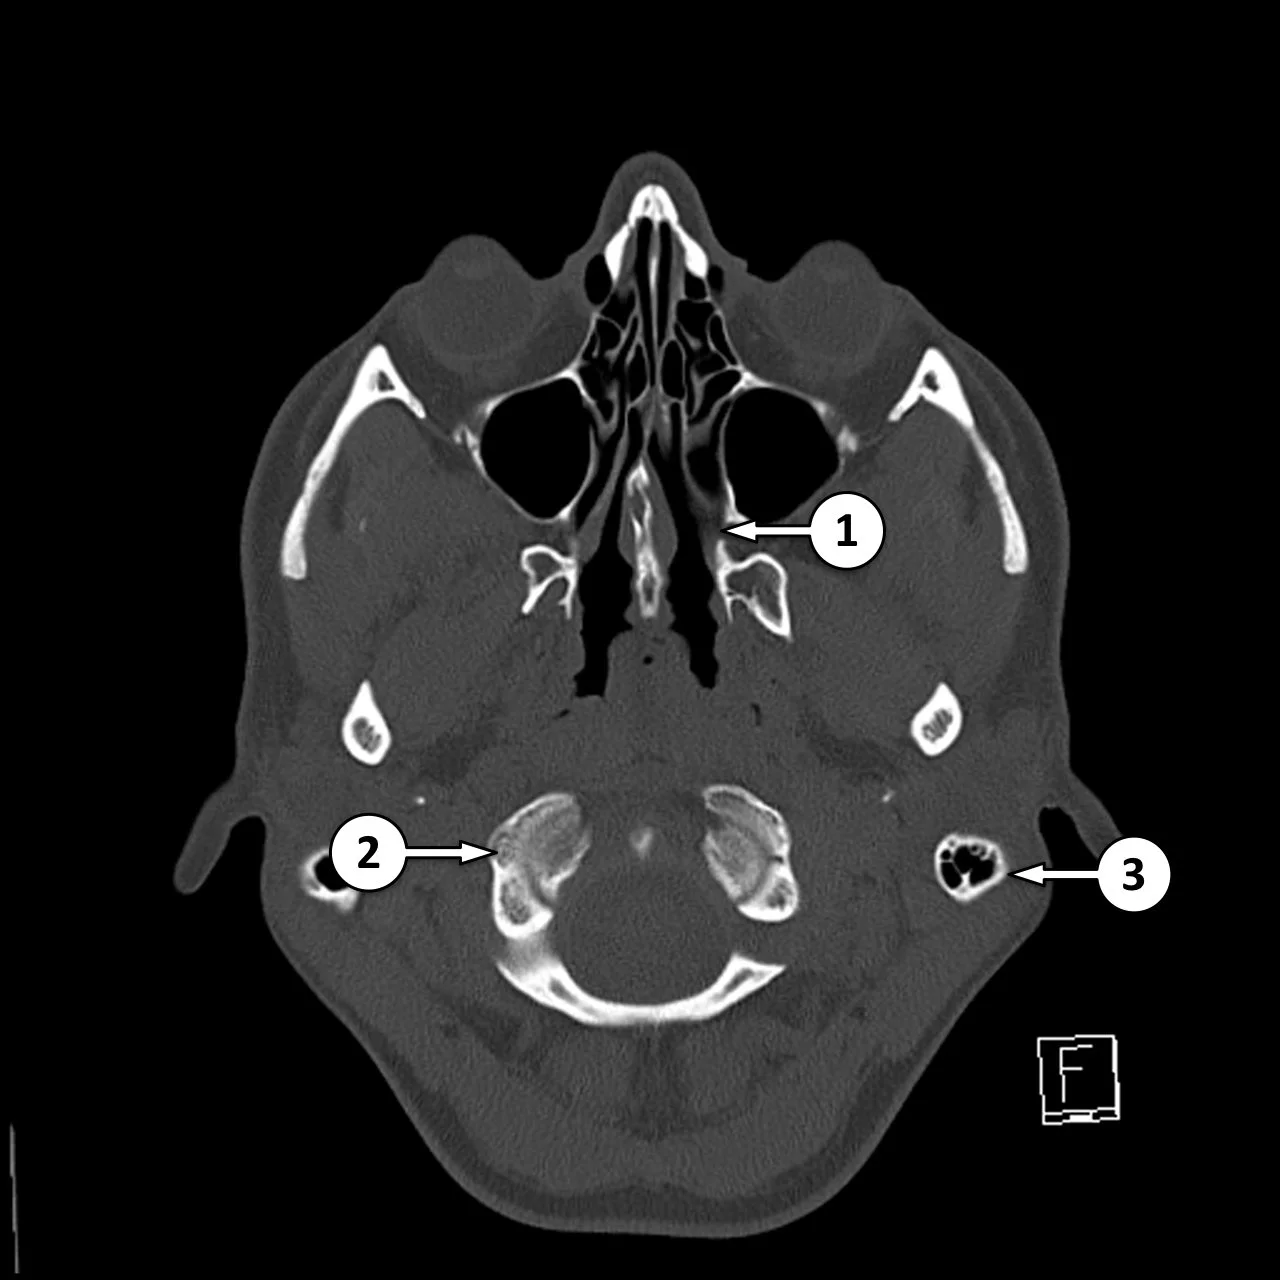

Sphenopalatine Foramen

• #1 in image to the right

• Allows passage of nasal cavity and pterygopalatine fossa

• Transmits

• Sphenopalatine artery & vein

• Nasopalatine nerve

• Posterior superior nasal nerves

• Clinical relevance

• Because nerves travel through here, it allows a possible passageway for peri-neural spread of malignancy from the nasal cavity to deeper structures